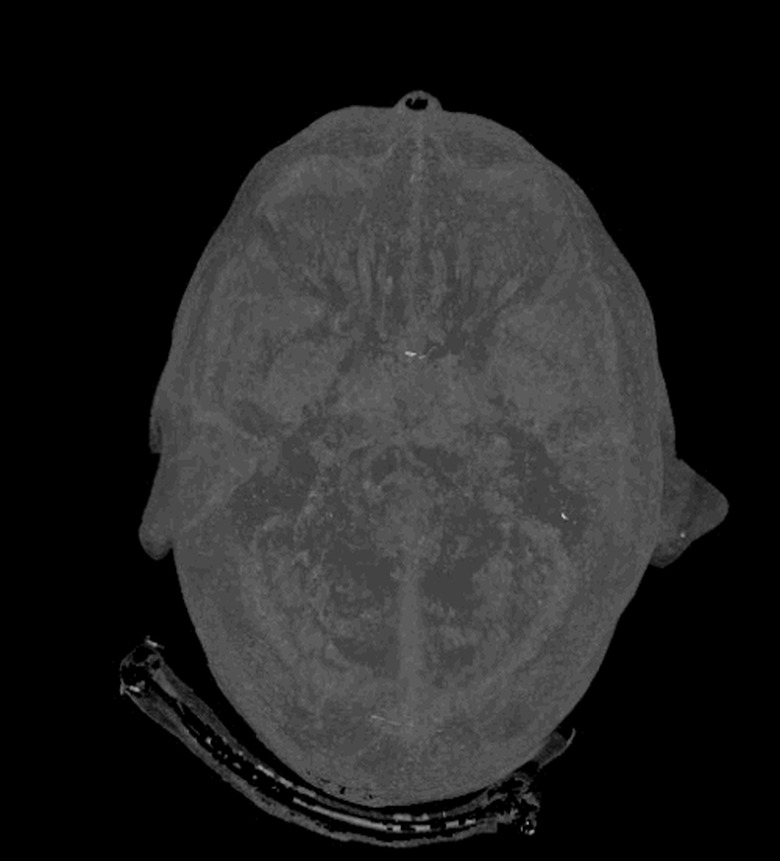

Few people enjoy having a CT scan. In a bleak hospital room, you have to lie flat on your back as a huge circular scanner shoots focused X-rays through your flesh and bones. The entire process can feel a little intimidating, which is why GE Healthcare has come up with the Revolution CT: a whisper-quiet and super-fast scanner that could make medical appointments a little quicker and less stressful for patients. The new machine, which is being trialled by the West Kendall Baptist Hospital in Florida, can capture an entire heart in a single beat, where each rotation takes just 0.28 seconds. That speed, combined with better contrast detection and noise reduction, could also reduce the doses of radiation required in each scan, potentially easing people's fears. In addition, none of these advancements should compromise the quality of the final 3D images — to prove its point, GE Healthcare has released some kinda gross, but undeniably beautiful GIFs of people's innards.

[Image Credit: GE Healthcare]